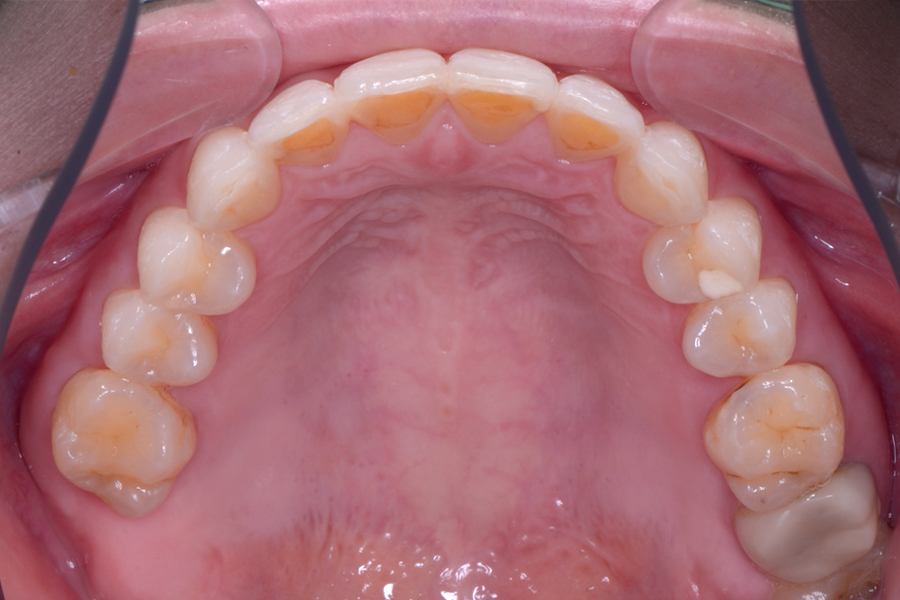

• 治療前